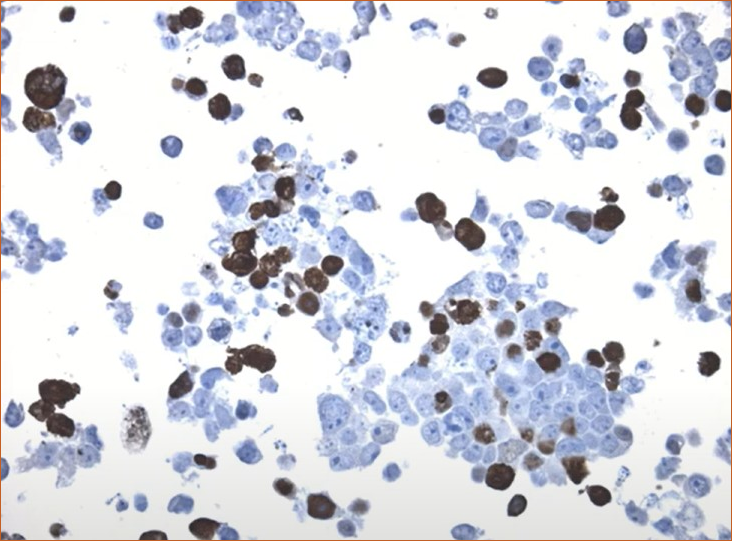

CytoSection control slides maintain the cellular localization patterns of nuclear and cytoplasmic/membrane-associated proteins, closely mirroring their distribution in tissue samples.

Cytoplasmic localization of DCC

DCC antibody of colon tissue. Image source: Protein atlas

DDK-tag detection of DCC in CytoSection ()